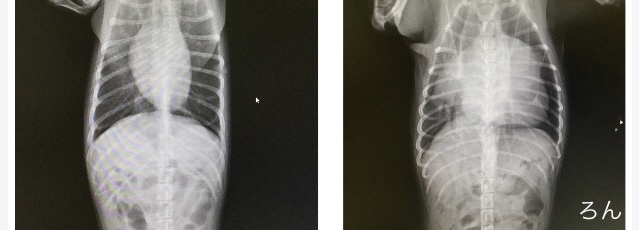

こちらは9月11日の心臓検査の診察結果です。写真を比較していただくと、心臓が大きく肥大しており気管を圧迫しているのが分かります。

正常な心臓

僧帽弁閉鎖不全症で肥大した心臓

肥大したろんの心臓